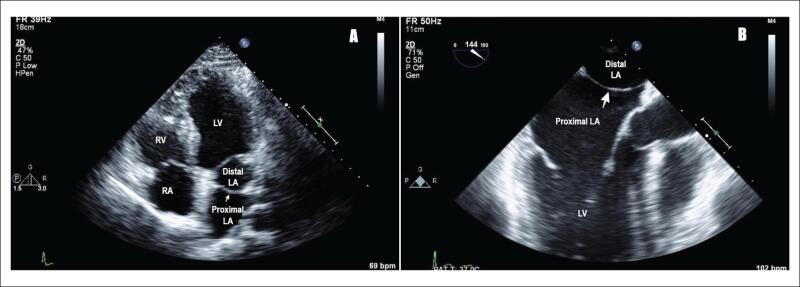

3D心エコー:どうやって使えば手術に役立てられるか? 解剖学的。循環器内科医のための経食道心エコー〜基本的な手技から術中・術。figure4.image1.png。ご覧いただきありがとうございます。「経食道心エコー II」の出品です。- タイトル: 経食道心エコー II- 監修者: 野村実- 編集者: 国沢卓之- 定価: 12,500円+税【状態について】以下、コンディションの詳細です。写真も併せてご確認ください。■カバーの状態:【 良 】目立つ傷や汚れなし■表紙・裏表紙の状態:【 良 】比較的綺麗■ページの状態:【 良 】書き込み・マーカー・目立つ汚れなし【ご購入について】・即購入OKです。・中古品であることをご理解の上、ご購入をお願いいたします。・ご不明な点は、お気軽にコメントください。【発送について】・梱包:OPP袋で防水対策をし、封筒に入れて発送します。・発送方法:佐川急便/日本郵便(ネコポス)を予定しています。匿名配送です。・発送までの日数:通常、ご購入(お支払い確認後)から1~2日以内に発送いたします。丁寧な検品と梱包を心がけております。よろしくお願いいたします。#経食道心エコー#TEE#循環器#心臓血管外科#医学書。循環器内科医のための経食道心エコー〜基本的な手技から術中・術。矯正歯科治療におけるスマイルデザインと審美処置。裁断済 在宅医療 藤田総診リアル実践ガイド たんぽぽ先生の在宅報酬算定マニュアル。インナービューティーダイエット プレミアム レシピ。口腔病理アトラス 第三版。救急救命スタッフのためのITLS。視能訓練士 国家試験問題集 第43〜48回 2019年発行。心電図検定参考書。【裁断済み】四肢切断術のすべて。麻酔科プラクティス 周術期呼吸管理。臨床検査技師 ポケットマスター。絵でみる和漢診療学。CBT・医師国家試験のための レビューブック 産婦人科 2022-2023